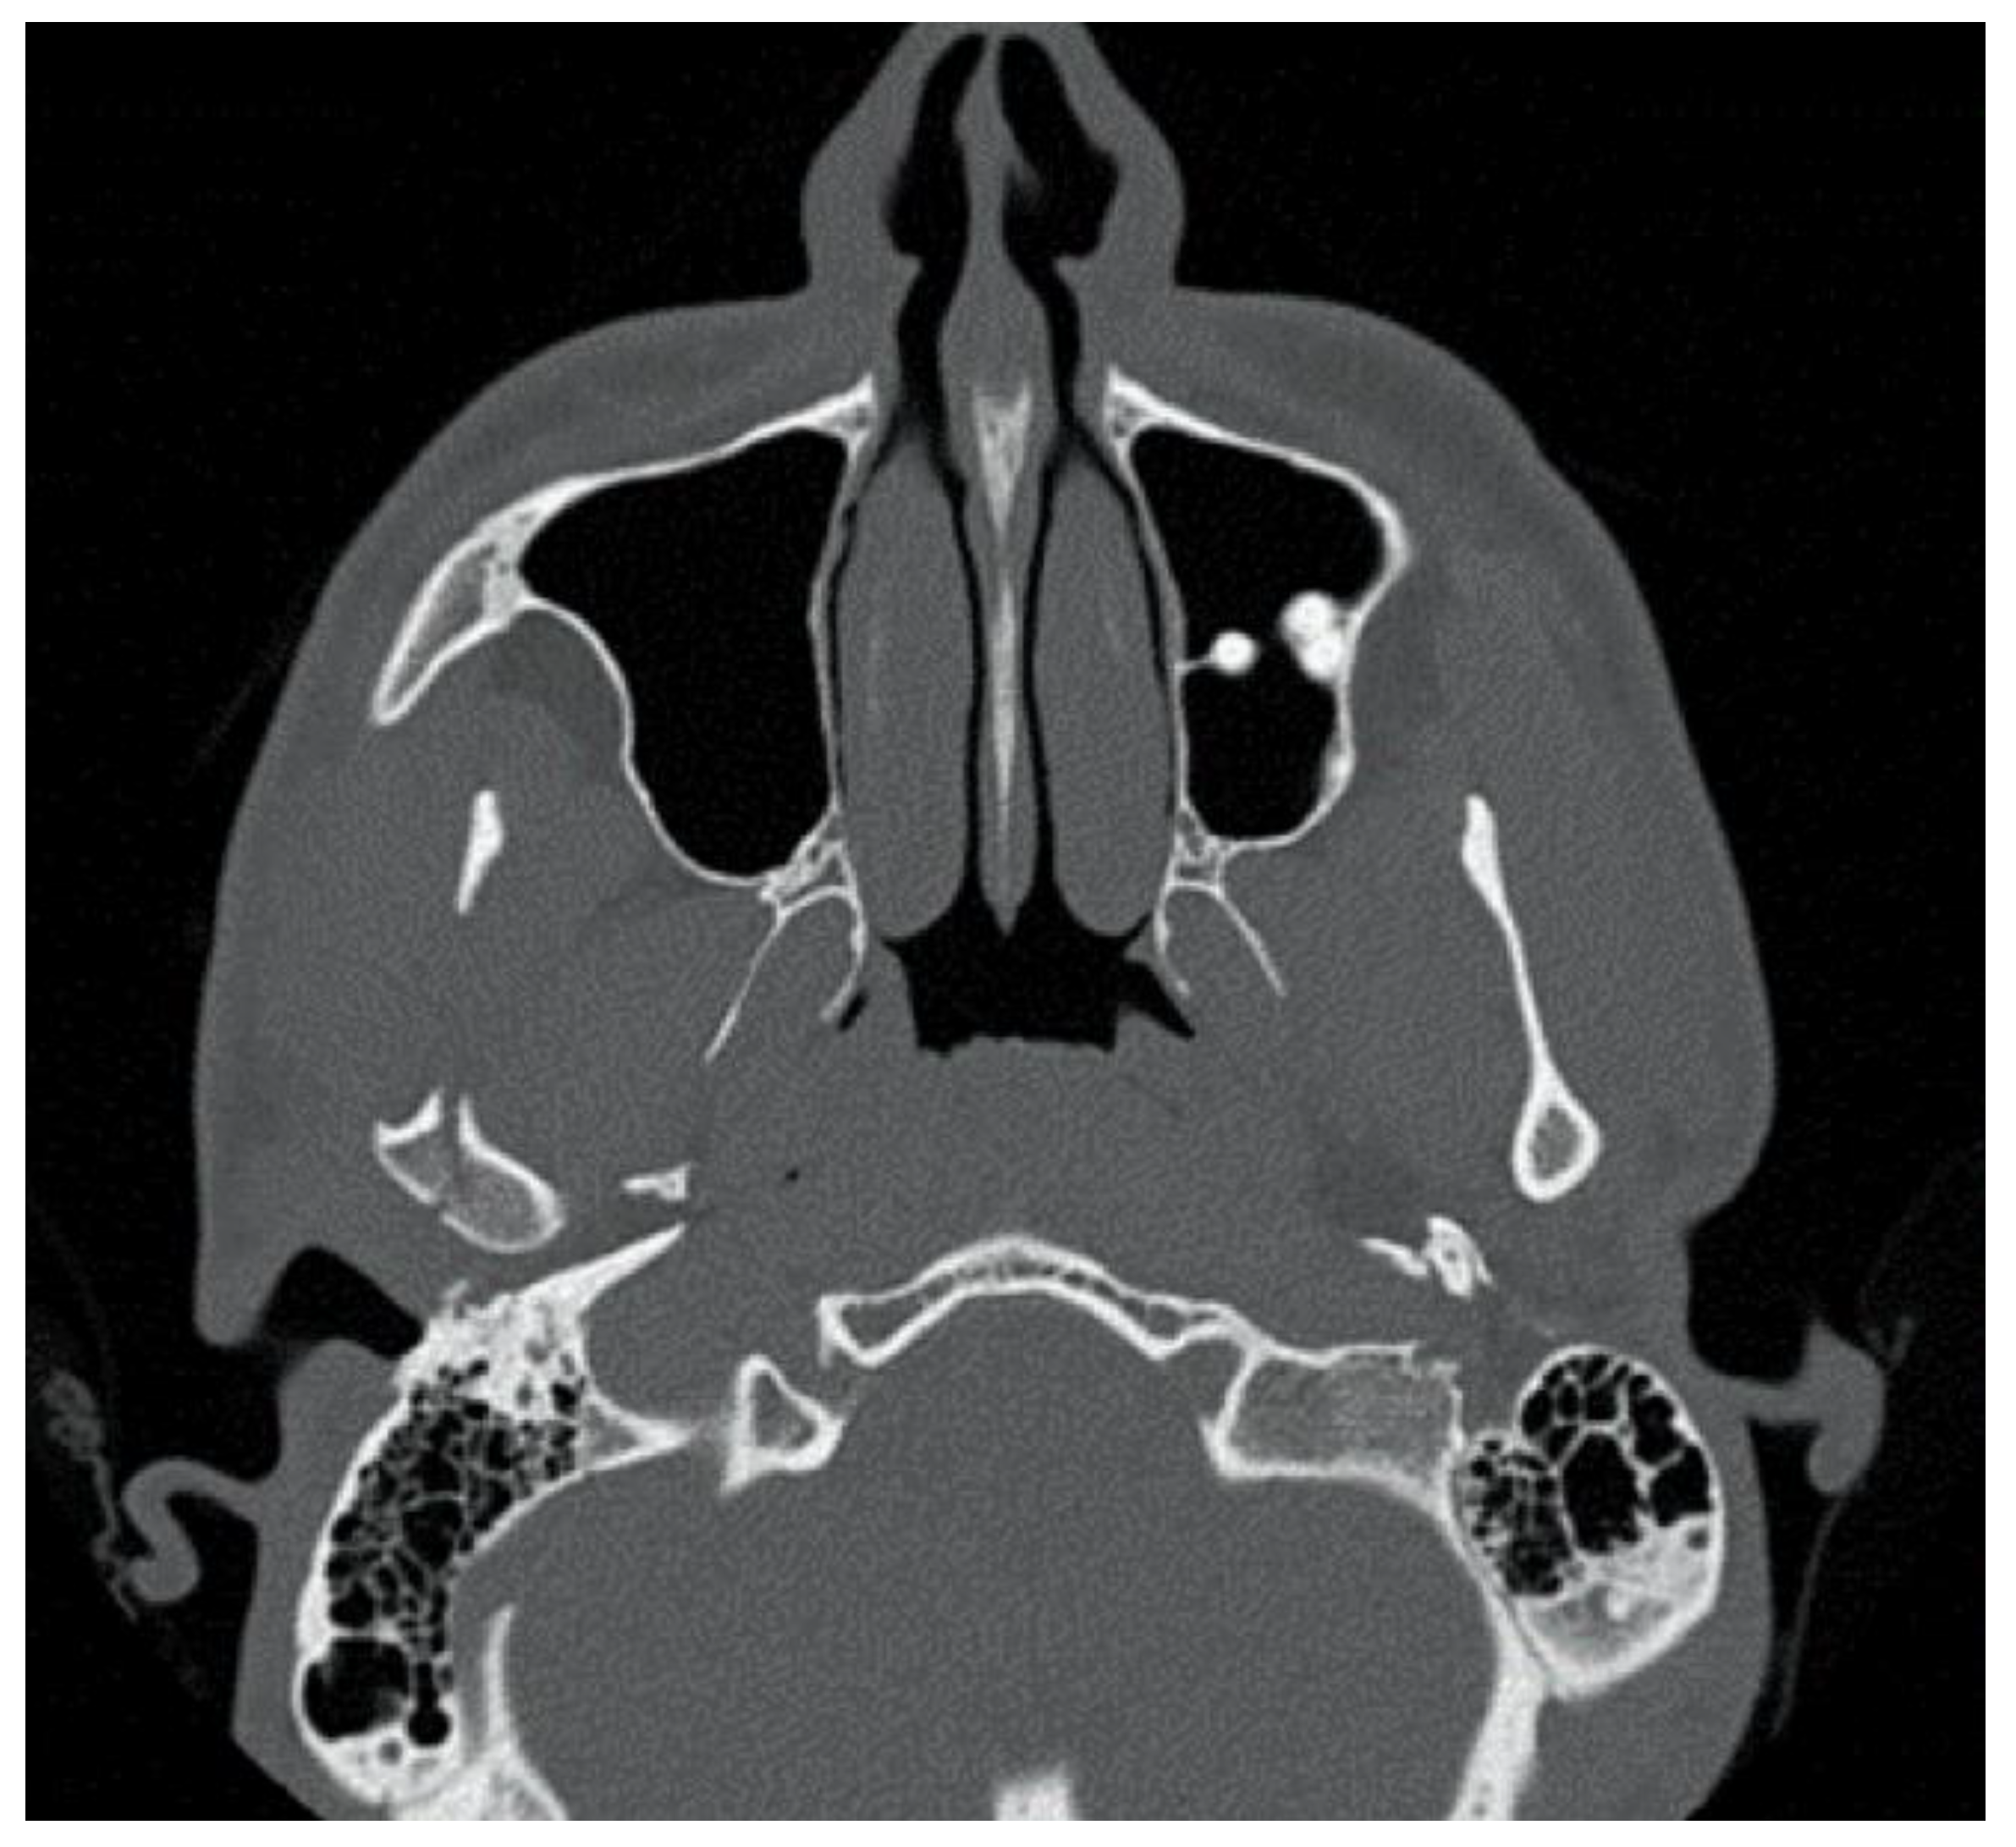

Figure 4. Patient 2, male, aged 20, with a right condylar diacapitular fracture.

The second patient was a male, aged 20, with a right condylar diacapitular fracture (Figure 4). The patient also presented a coronal fracture of the element 43 due to the trauma. The other teeth were sound, but the 37 was unerupted. He presented a slight class III malocclusion and a posterior open bite on the left. In this case, there was the need to not exert force on the fractured tooth, and to balance the traction points of the rubber bands despite the absence of the 37, avoiding extrusive forces on the 27.